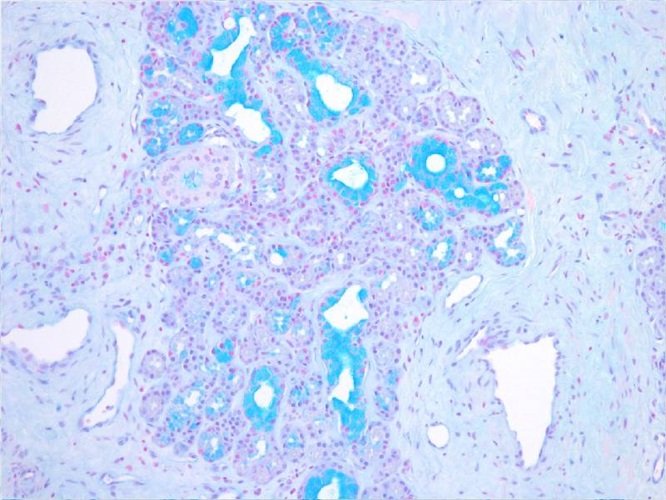

Комплект постачає реагенти для виявлення кислотних муцинів та мукосубстанцій. Висока концентрація кислотних мукосубстанцій спостерігається при мезотеліомі. Висока концентрація мукосубстанцій зазвичай виявляється в стінках кровоносних судин, але збільшується при ранніх ураженнях атеросклерозу.